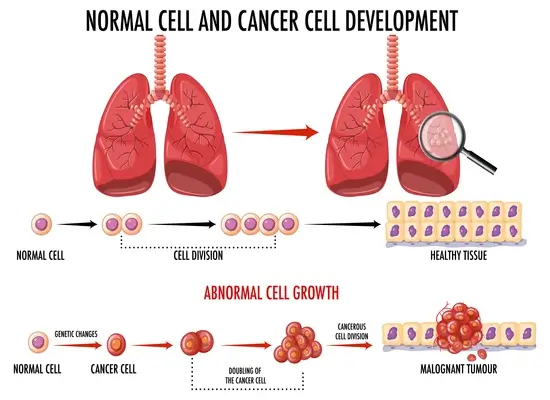

फेफड़ों का कैंसर क्या है?

फेफड़ों का कैंसर, फेफड़ों में शुरू होता है और यह तब होता है, जब फेफड़ों में कोशिकाएँ अनियंत्रित तरीके से विभाजित होकर ट्यूमर के रूप बढ़ने लगती हैं। ट्यूमर व्यक्ति की सांस लेने की क्षमता को प्रभावित कर सकते हैं और वे शरीर के अन्य भागों में भी फैल सकते हैं।